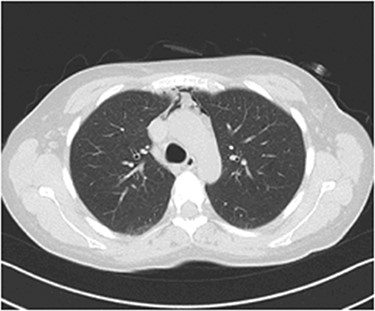

The possibility of pulmonary embolism was put first on the differential diagnosis list. In order to exclude this life-threatening complication, D-dimers and computed angiography of the pulmonary arteries were performed. Computed Tomography of the Pulmonary Arteries (CTPA) (Fig. 1) showed normal contrast enhancement of the pulmonary arteries, with no contrast deficits. Nevertheless, it brought out the presence of gas inside the mediastinum (capnomediastinum). Consequently, the D-dimers came out negative.

CTPA images show the presence of gas in the upper anterior mediastinum.